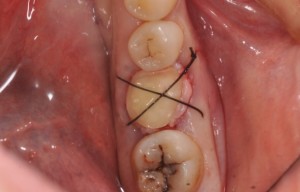

十字縫合とは字の通り

傷口に対して十字に

縫い合わせることで

創傷治癒促進や

傷が目立たないように治癒する

サポートをします!

主に親知らずの抜歯後に

用いられることが多いです!

抜いた後の穴(抜歯窩と言います)が

大きい時などに、

この縫合することが

多いです!